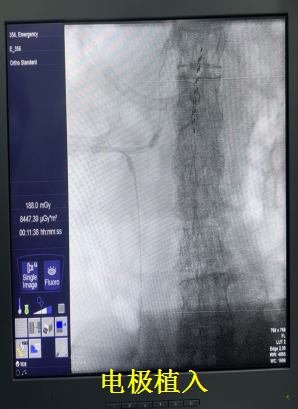

西院二病区尚亮主任团队在了解到患者的情况后,卫娜副主任立即组织多学科专家会诊。鉴于患者的特殊情况,神经外科缪星宇主任与张翼博士等团队成员,经过精准评估和充分讨论,决定采用脊髓电刺激镇痛疗法。该疗法通过在脊髓硬膜外腔植入电极,将外界电刺激传递到脊髓,干扰疼痛信号传导,从而达到缓解疼痛的目的。其具有创伤小、可逆、可调节等优点,特别适合高龄、身体状况较差的患者。

为了确保治疗的安全性和有效性,神经外科与西院二病区结合患者的实际情况,制定了个性化的精准治疗方案。从围手术期的管理、电极的植入位置到刺激参数的设置,每一个环节都经过精心设计和反复调试。同时,团队医护人员密切关注老人心理状态,耐心解释治疗原理和过程,缓解患者及家属的紧张焦虑情绪。

局部麻醉后,手术顺利进行,电极成功植入到预定位置。当开启脊髓电刺激设备的那一刻,老人惊喜地发现,折磨他多年的疼痛竟然减轻了一大半。他激动地表示:“好久没有这么轻松了。” 术后,尚亮主任团队和缪星宇主任团队每日查看患者恢复情况,根据患者感受及时调整刺激参数,确保治疗达到最佳效果。